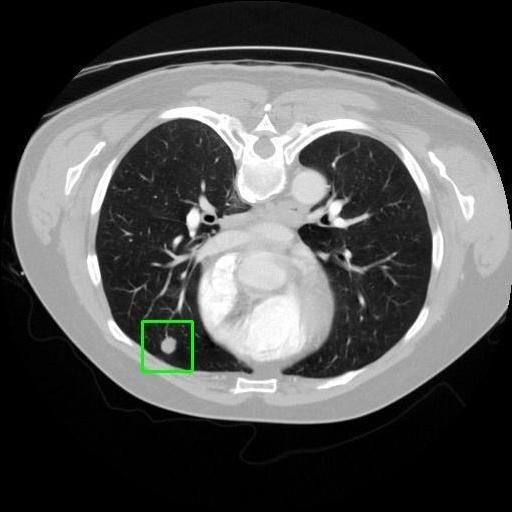

We developed an AI-based system using deep learning models for analyzing lung CT scans to detect and classify pulmonary nodules. We chose the YOLOv11 architecture for its enhanced object detection capability and adapted it specifically for medical imaging, incorporating pixel-level precision and severity classification.

Classification into three severity levels with colored bounding boxes.

Successfully built and deployed an AI model (YOLOv11) capable of detecting lung nodules in CT scans with high accuracy and real-time performance.

Designed a severity classification system that categorizes nodules into null, moderate, and severe using colored bounding boxes, assisting in rapid clinical decision-making.